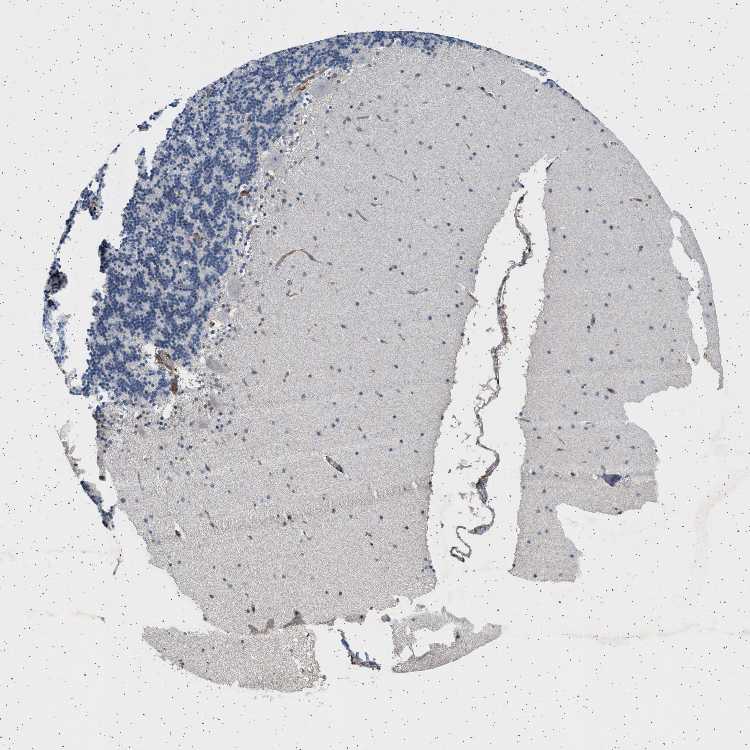

CEREBELLUM - Antibody stainingi

Antibody staining in the annotated cell types in the current human tissue is reported as not detected, low, medium, or high, based on conventional immunohistochemistry profiling in selected tissues. This score is based on the combination of the staining intensity and fraction of stained cells.

Each image is clickable and will lead to virtual microscopy that enables deeper exploration of all samples and also displays staining intensity scores, fraction scores and subcellular localization as well as patient and tissue information for each sample.

Antibody HPA018096

Purkinje cells Not detected

Cells in granular layer Not detected

Cells in molecular layer Not detected